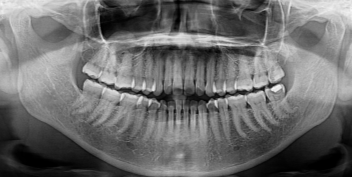

Many patients experience severe discomfort when their wisdom teeth become impacted. An impacted tooth occurs when the tooth does not have enough space to erupt fully and becomes trapped under the gum or bone. This condition may cause swelling, jaw stiffness, infection, bad breath, and persistent pain. In such cases, impacted wisdom tooth removal becomes necessary to prevent further complications and protect surrounding teeth. At Dental Lifecare in Sector 71, Noida, patients receive precise diagnosis using modern digital imaging before proceeding with wisdom tooth surgery

When a wisdom tooth cannot erupt properly or is causing damage to nearby teeth, dentists recommend wisdom tooth extraction Noida or third molar extraction Noida. The procedure may involve either a simple extraction or a minor surgical procedure depending on the position of the tooth. At Dental Lifecare in Sector 71, Noida, the focus is on providing painless removal of third molar Noida using advanced anesthesia techniques and minimally invasive surgical methods. This approach ensures patient comfort, faster healing, and minimal swelling after the procedure.

Patients often worry about the complexity of wisdom tooth surgery Noida, but with an experienced dentist the procedure becomes safe and predictable. Dr. Vijay Prakash Gupta, with 22 years experience, carefully evaluates the tooth position, nerve proximity, and jaw structure before performing third molar extraction Noida. His expertise ensures that patients receive safe treatment with minimal discomfort.